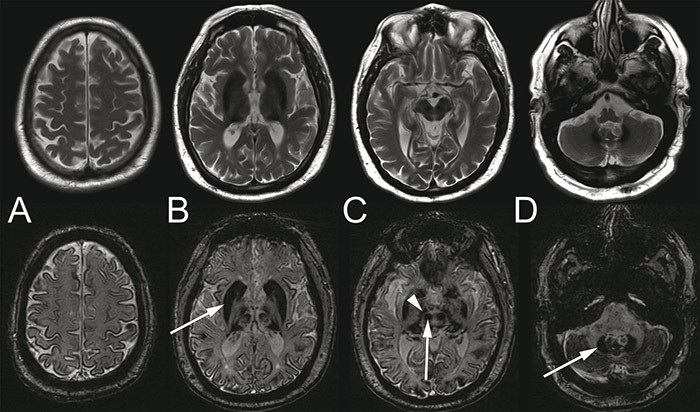

Neurological examination revealed unsteady gait, ataxia in the knee-heel test, abnormal performance in the finger-nose test, intention tremor and slow saccades, which could indicate cerebellar disease. MRI of the head revealed widespread iron deposits in the cerebral cortex, brainstem nuclei and basal ganglia (Fig. 1), but not in the meninges. Cerebrospinal fluid was normal, apart from slightly elevated total protein. Examination of dementia markers revealed a non-specific increase in tau protein and normal β-amyloid.

Figure 1  Cerebral MRI of the patient in his late 50s. T2-weighted (upper row) and susceptibility-weighted (SWI, bottom row)…

Figure 1 Cerebral MRI of the patient in his late 50s. T2-weighted (upper row) and susceptibility-weighted (SWI, bottom row) series. SWI is significantly more sensitive to iron deposition than the T2 series. There is widespread and symmetrical iron deposition, with deposits revealed by hypointensities in the cerebral (A) and cerebellar cortex (D), striatum (arrow in B), red nucleus and substantia nigra (arrow and arrowhead in C) and the dentate nucleus of the cerebellum (arrow in D)

The patient had iron deposition centrally in the brain, with progressive neurological symptoms and pathology in several areas of the central nervous system, including the retina. This combination of neurological symptoms plus iron accumulation in the brain and other organs is seen in a number of distinct progressive conditions known as «neurodegeneration with brain iron accumulation» (NBIA) (6, 7). In these disorders, the accumulation of iron in the brain, particularly in the basal ganglia, can most easily be seen in T2-weighted and susceptibility-weighted MR images (SWI).